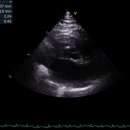

동물메디컬센터 ​ 고양이 심장병이란? 고양이 심장병 증상은 호흡곤란, 기침, 기력저하, 식욕 부진 등이 있다. ​ 특히 HCM (비대성심근증성)이 고양이 심장병 중 제일 흔한 질병이다. ​ 심장 근육이 비정상적으로 두꺼워지는 질환을 말한다. ​ 나이, 품종, 성별 상관없이 발생할 수 있지만 유전 영향이 크기 때문에 *일부...